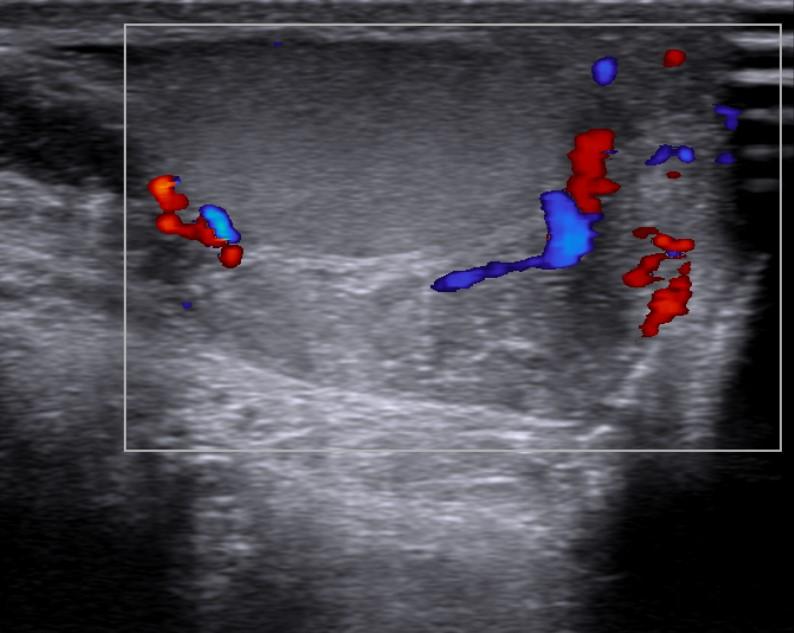

Case of the Week 31 2016 *33-year-old male with pain in left testicle. What is the most likely diagnosis? Answer Answer: Epididymitis Kategori:Cases Önceki yazı Case of the Week 6 2016 Sonraki yazı Case of the Week 17 2016